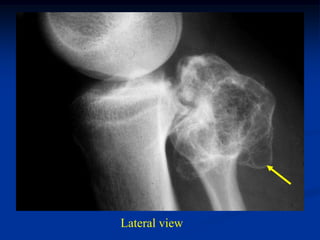

Case #556

55 year male with

enchondroma tibia

Lateral view